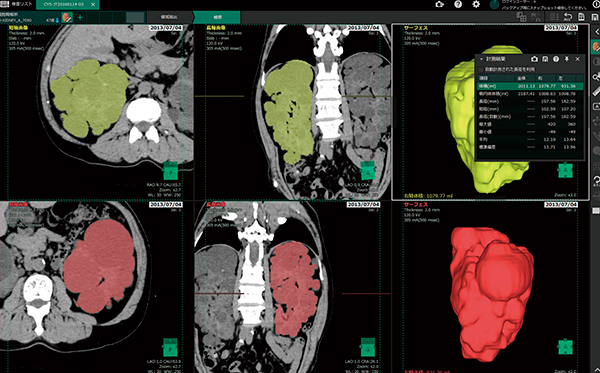

従来の抽出法では,単純CT画像から囊胞を含む腎臓領域を,ユーザーが指定した腎臓の長径をベースに,腎臓は楕円球のような形状をしていると仮定した腎領域抽出を行っていた。しかし,ユーザーが設定する長径箇所により抽出結果に差が出るため,再現性の低下という点で問題を抱えていた。最新のバージョンでは,ディープラーニングを用いて設計した臓器抽出機能を実装し,ユーザー操作介入なしで,囊胞を含む腎臓領域を認識するように改良している。これにより腎臓体積の増加,減少率の管理を客観的に行うことができ,その結果も囊胞腎解析のレポートとして出力することができるようになっている(図5)。

図5 囊胞腎解析画面

病状が進んで腎臓の形状が正常から大幅に逸脱した場合でも,腎臓を腎臓領域として認識する。